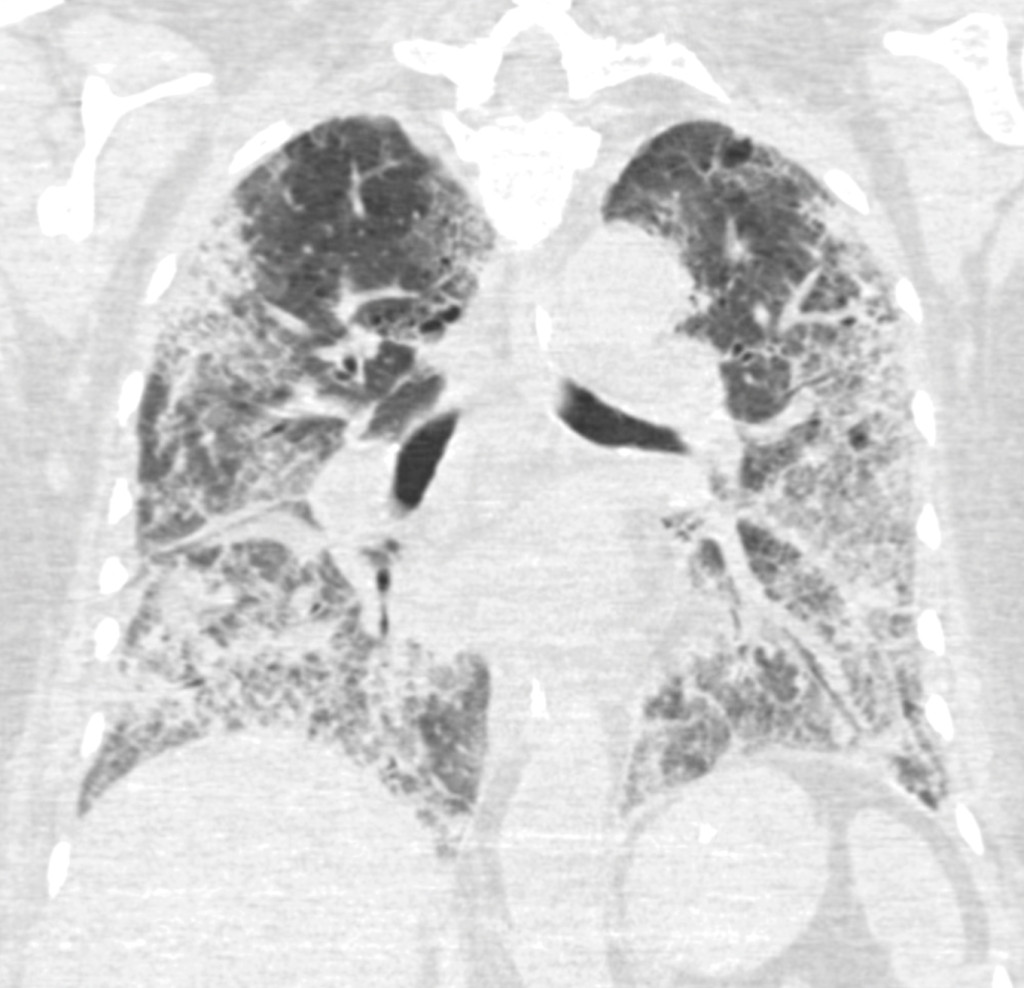

Eighteen days after hospitalisation, a CT scan (Figure 2) showed bilateral pulmonary opacities and peripheral pulmonary embolisms. The prophylactic dose of anticoagulant that the patient had been given since she was placed on a ventilator (dalteparin 5 000 U x 1 subcutaneously), was therefore increased to a weight-adjusted therapeutic dose for pulmonary embolisms (12 500 U x 1 subcutaneously). Her CRP value remained high despite broad-spectrum antimicrobial therapy, and for the third time the patient required extensive O2 support, with unchanged ventilatory input.

Figure 2 Frontal CT thorax section taken 28 days after onset of symptoms, 17 days after hospitalisation and 14 days after…

Figure 2 Frontal CT thorax section taken 28 days after onset of symptoms, 17 days after hospitalisation and 14 days after the patient was placed on a ventilator. At the time the patient still had considerable need for ventilation. The image shows extensive ground-glass opacities with peripheral and basal distribution and crazy paving pattern.